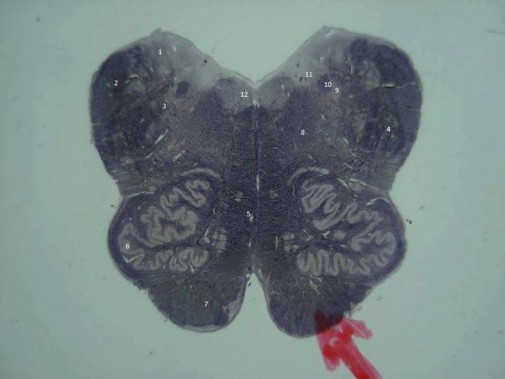

1. Núcleos Vestibulares; 2. Pedúnculo Cerebelar Inferior; 3. Núcleo do Trato Espinal do Nervo Trigêmeo; 4. Trato Espinhal do Nervo Trigêmeo; 5. Lemnisco Medial; 6. Núcleo Olivar Inferior; 7. Pirâmide; 8. Formação Reticular; 9. Núcleo do Trato Solitário; 10. Trato Solitário; 11. Núcleo Dorsal do Nervo Vago; 12. Núcleo do Nervo Hipoglosso

Corte de Bulbo na Região mais rostral